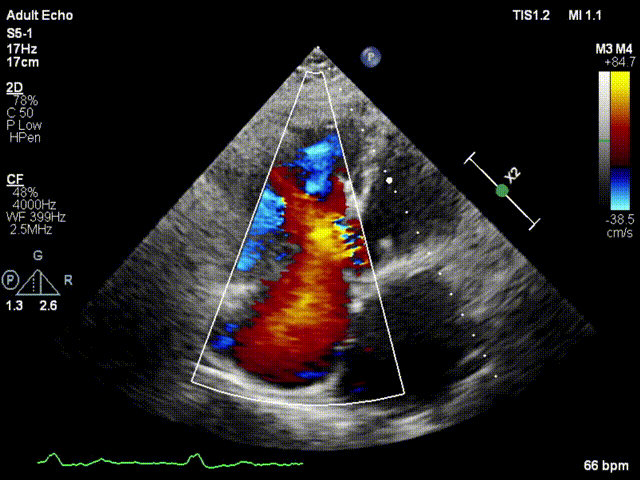

本次接受治療的患者是一名74歲的女性,14年前因風(fēng)濕性心臟病行二尖瓣生物瓣植入術(shù),合并房顫。近3年來反復(fù)因腹脹、納差、下肢水腫入院,藥物治療欠佳。心臟超聲顯示三尖瓣極重度反流(有效反流口面積:0.76cm²,反流容積:79ml),繼發(fā)性右房室增大及上、下腔靜脈增寬(右房上下徑*左右徑:52*41mm,右室左右徑:46mm,下腔靜脈:29mm),右室收縮功能正常,肺動(dòng)脈收縮壓 43mmHg,左心室射血分?jǐn)?shù)73% ?;颊呒韧_胸手術(shù)史,術(shù)前評估STS 評分為7.02分,CRS 9分,無法接受體外循環(huán)下三尖瓣外科手術(shù)。面對這一傳統(tǒng)治療無法解決的困境,葛均波院士及其團(tuán)隊(duì)周達(dá)新教授、潘文志教授、張?jiān)床┦俊㈥惿┦考靶某业呐舜湔浣淌?、李偉教授?jīng)過討論決定,采用創(chuàng)新的Lux-Valve Plus系統(tǒng)為患者進(jìn)行經(jīng)血管三尖瓣置換。

手術(shù)在患者全麻狀態(tài)下進(jìn)行,采用經(jīng)右側(cè)頸靜脈作為入路,將裝載有人工瓣膜的輸送器緩慢推送至右心房;并在經(jīng)食道超聲和DSA的引導(dǎo)下小心調(diào)整輸送器角度,將輸送器送入右心室;逐步釋放瓣膜錨定裝置和盤片,調(diào)整瓣膜位置后,錨定瓣膜完成植入。術(shù)后右房壓明顯下降,從術(shù)前的25/10(16) mmHg降至術(shù)后即刻的12/7(10) mmHg,術(shù)后超聲提示人工三尖瓣同軸性良好,固定牢固,無反流及瓣周漏,手術(shù)室即刻拔除氣管插管。